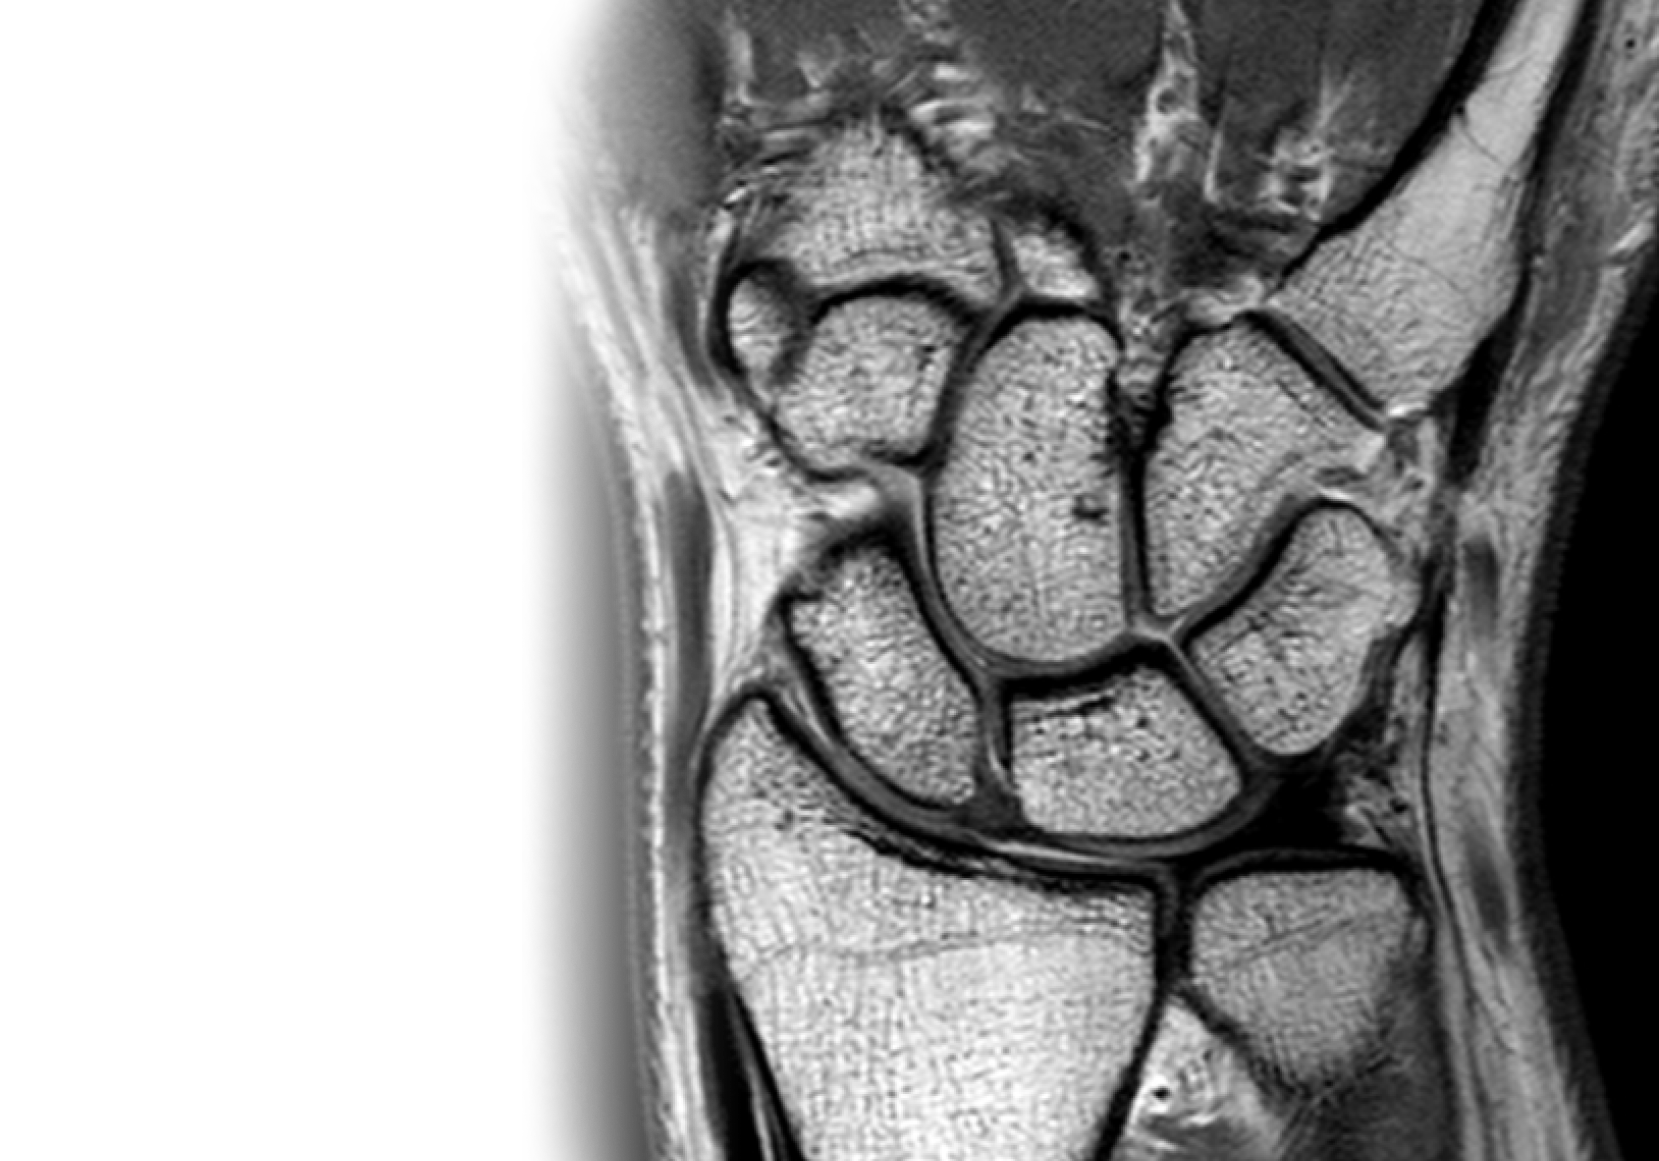

МРТ лучезапястного сустава МРТ лучезапястного сустава

МРТ лучезапястного сустава

Магнитно-резонансная томография лучезапястного сустава – важный метод исследования, который позволяет оценить состояние лучезапястного сустава.